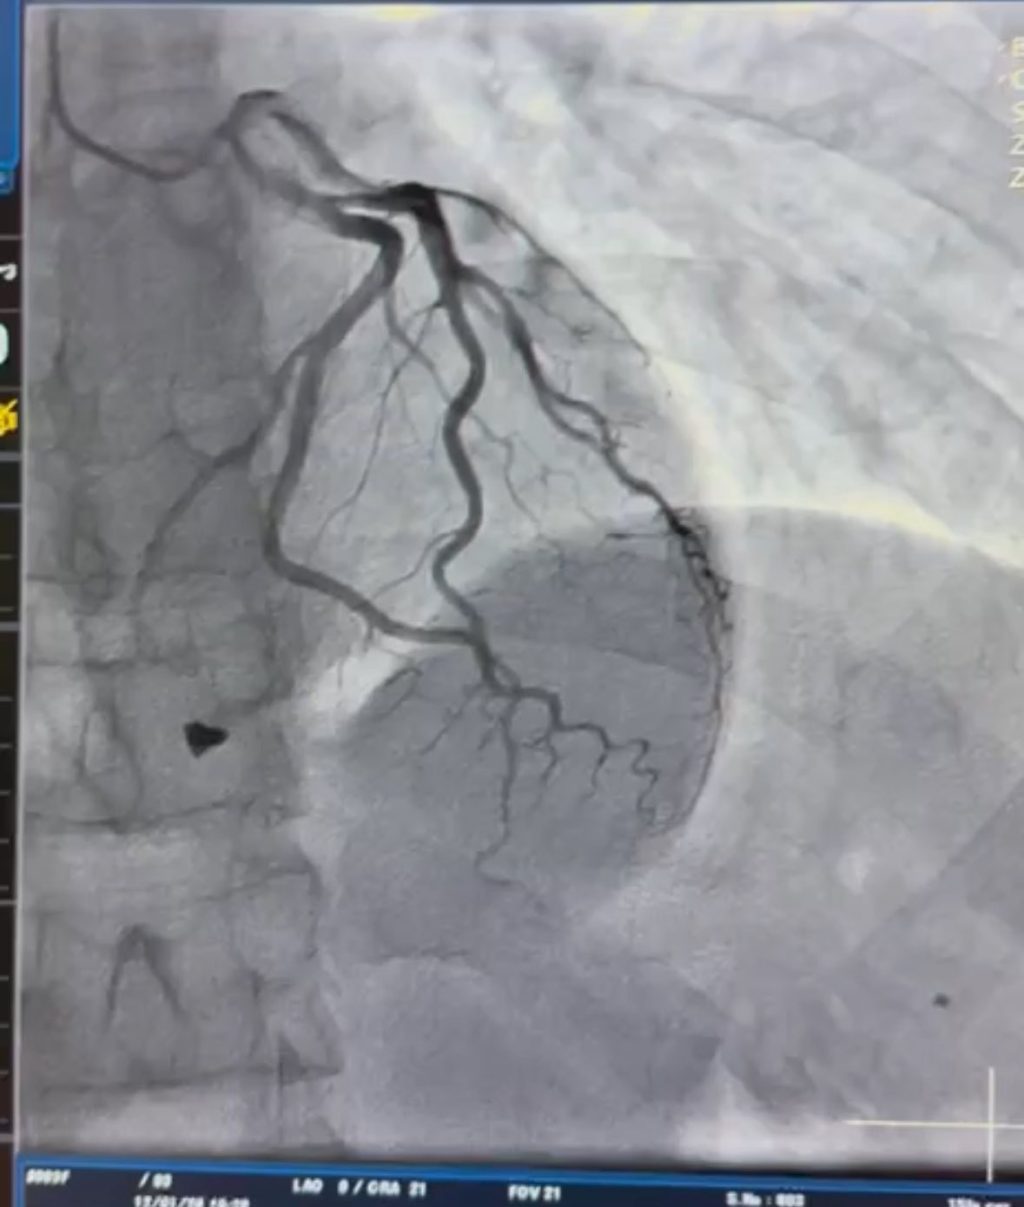

Під час обстеження пацієнта медики встановили, що металевий уламок локалізувався в зоні клапанного апарату серця з пошкодженням папілярного м’яза тристулкового клапана, що створювало загрозу порушення його повноцінної роботи. Повідомляє Вінниччина Онлайн з посиланням на КНП “Вінницька обласна клінічна лікарня імені М. І. Пирогова“.

Після детального аналізу характеру травми кардіохірургічна команда закладу провела видалення вогнепального осколка та виконала пластику тристулкового клапана. Завдяки оперативному втручанню вдалося відновити функцію клапана та забезпечити стабільну роботу серця.

За інформацією медиків, подібні поранення належать до найскладніших у сучасній кардіохірургії та потребують точної передопераційної візуалізації, злагодженої роботи мультидисциплінарної команди, а також високого рівня кардіохірургічної й анестезіологічної експертизи.